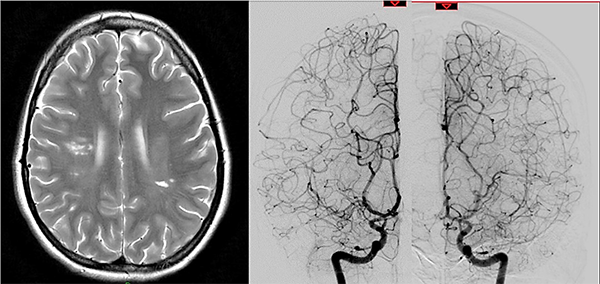

Caso clínico #1: PR masculino de 20 años sin antecedentes clínicos, estudiado por cefaleas de varios meses de evolución. La RMN no presenta lesiones y la ARM evidencia una disminución del flujo de la arteria cerebral media derecha. La ADC muestra la estenosis progresiva de la arteria carótida interna derecha supraclinoidea, ausencia de opacificación del origen de la arteria cerebral media y anterior, presencia de vasos de MM con escasa circulación colateral desde carótida interna izquierda a través de la comunicante anterior; corresponde a un grado 3 de Suzuki (Fig. 1). Se realizó una revascularización cerebral combinada: un bpTS más EDMS derecho, la evolución postoperatoria fue sin complicaciones y la ADC diferida muestra una buena perfusión cerebral a través del bypass y la sinangiosis (Fig. 2). El control clínico a 4 años es favorable y las imágenes de RMN y RMA evidencian ausencia de nuevas lesiones isquémicas y adecuada revascularización.

Fig. 1 Caso clínico #1. ARM y ADC preoperatoria, obsérvese la estenosis progresiva de la arteria carótida supraclinoidea derecha con ausencia del origen de las arterias cerebral anterior y media. Corresponde a un grado 3 de Suzuki